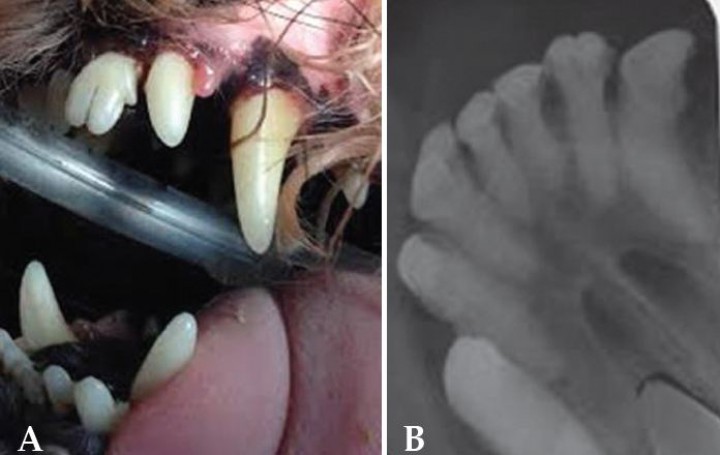

Quiste dentígero /quiste folicular

Se trata de una estructura quística que se origina de forma secundaria a un diente no erupcionado (impactado o incluido).[ Brook AN. Pathology in the pediatric patient. En: Niemiec B: Small Animal Dental, Oral and Maxillofacial Disease. Manson Publishing. London 2010; 90-123. , Wiggs RB, Lobprise HB. Veterinary Dentistry, Principles and Practice. Lippincott-Raven, Philadelphia. 1997; 130; 440-444; 472-474 . , Neville BW, Damm DD, Allen CM, Bouquot JE. Oral and Maxillofacial Pathology. WB Saunders, Philadelphia. 2002. ]

El esmalte se forma y desarrolla antes de la erupción dentaria por el órgano formador de esmalte o folículo, integrado en unas células llamadas ameloblastos.[ Brook AN. Pathology in the pediatric patient. En: Niemiec B: Small Animal Dental, Oral and Maxillofacial Disease. Manson Publishing. London 2010; 90-123. , Whyte A, Whyte J, Sopena J, et al. Atlas de Odontología en pequeños animales. Edimsa. Madrid 1998; 42. ] Si el diente erupciona de manera convencional, el órgano formador de esmalte se desgasta rápidamente. Si por el contrario un diente no erupciona, los ameloblastos persisten y forman una estructura en forma de saco revestida de epitelio.[ Brook AN. Pathology in the pediatric patient. En: Niemiec B: Small Animal Dental, Oral and Maxillofacial Disease. Manson Publishing. London 2010; 90-123. , Wiggs RB, Lobprise HB. Veterinary Dentistry, Principles and Practice. Lippincott-Raven, Philadelphia. 1997; 130; 440-444; 472-474 . ] Este epitelio puede ser, o no, productivo. En la mayor parte de los casos produce líquido y dará lugar a una formación quística.[ Brook AN. Pathology in the pediatric patient. En: Niemiec B: Small Animal Dental, Oral and Maxillofacial Disease. Manson Publishing. London 2010; 90-123. , Neville BW, Damm DD, Allen CM, Bouquot JE. Oral and Maxillofacial Pathology. WB Saunders, Philadelphia. 2002. ] Es importante resaltar que no todos los dientes no erupcionados desarrollarán quistes.[ Brook AN. Pathology in the pediatric patient. En: Niemiec B: Small Animal Dental, Oral and Maxillofacial Disease. Manson Publishing. London 2010; 90-123. ]

Estas estructuras se pueden presentar en la dentadura de leche, pero son más comunes en la permanente. Cuando su tamaño es reducido, generalmente son asintomáticos, pudiendo apreciarse áreas de inflamación en zonas desprovistas de dientes.[ Brook AN. Pathology in the pediatric patient. En: Niemiec B: Small Animal Dental, Oral and Maxillofacial Disease. Manson Publishing. London 2010; 90-123. ] Si por el contrario el quiste alcanza gran tamaño, puede originar una pérdida ósea significativa o destrucción de tejidos adyacentes en función de la presión ejercida.[ Brook AN. Pathology in the pediatric patient. En: Niemiec B: Small Animal Dental, Oral and Maxillofacial Disease. Manson Publishing. London 2010; 90-123. , Wiggs RB, Lobprise HB. Veterinary Dentistry, Principles and Practice. Lippincott-Raven, Philadelphia. 1997; 130; 440-444; 472-474 . , Neville BW, Damm DD, Allen CM, Bouquot JE. Oral and Maxillofacial Pathology. WB Saunders, Philadelphia. 2002. ] En ambos casos pueden producirse infecciones[ Brook AN. Pathology in the pediatric patient. En: Niemiec B: Small Animal Dental, Oral and Maxillofacial Disease. Manson Publishing. London 2010; 90-123. , Neville BW, Damm DD, Allen CM, Bouquot JE. Oral and Maxillofacial Pathology. WB Saunders, Philadelphia. 2002. ] (a veces son confundidos con abscesos) y neoplasias como el ameloblastoma[ Brook AN. Pathology in the pediatric patient. En: Niemiec B: Small Animal Dental, Oral and Maxillofacial Disease. Manson Publishing. London 2010; 90-123. , Neville BW, Damm DD, Allen CM, Bouquot JE. Oral and Maxillofacial Pathology. WB Saunders, Philadelphia. 2002. , Kramek BA, O’Brien TD, Smith FO. Diagnosis and removal of a dentygerous cyst complicated byan ameloblastic fibro-odontoma in a dog. J Vet Dentistry 1996, 13(1):9-11. [PMC] , Castelló P, Borrego J, Ortega J. Clasificación, diagnóstico y tratamiento de los tumores odontogénicos. Clín Vet Peq Anim 2014; (34) 4:194-200. ] y carcinoma de células escamosas.[ Brook AN. Pathology in the pediatric patient. En: Niemiec B: Small Animal Dental, Oral and Maxillofacial Disease. Manson Publishing. London 2010; 90-123. , Neville BW, Damm DD, Allen CM, Bouquot JE. Oral and Maxillofacial Pathology. WB Saunders, Philadelphia. 2002. ]

El diagnóstico se realiza mediante radiología[ Brook AN. Pathology in the pediatric patient. En: Niemiec B: Small Animal Dental, Oral and Maxillofacial Disease. Manson Publishing. London 2010; 90-123. , Neville BW, Damm DD, Allen CM, Bouquot JE. Oral and Maxillofacial Pathology. WB Saunders, Philadelphia. 2002. ] (se debe radiografiar cualquier zona de ausencia dental). Revelan un área radiolúcida asociada a la corona de un diente no erupcionado (Fig. 10). El diagnóstico definitivo es a través de anatomía patológica.[ Brook AN. Pathology in the pediatric patient. En: Niemiec B: Small Animal Dental, Oral and Maxillofacial Disease. Manson Publishing. London 2010; 90-123. ]

<p>A. Se observa la ausencia del canino inferior derecho (404). El segundo premolar inferior derecho (406) no ha erupcionado completamente. B. Radiografia lateral oblicua de la mandíbula. Se aprecia la presencia de un quiste dentígero secundario a un diente no erupcionado (impactado o incluido).</p>

A. Se observa la ausencia del canino inferior derecho (404). El segundo premolar inferior derecho (406) no ha erupcionado completamente. B. Radiografia lateral oblicua de la mandíbula. Se aprecia la presencia de un quiste dentígero secundario a un diente no erupcionado (impactado o incluido).

Debemos hacer diagnóstico diferencial de neoplasias, abscesos, otros crecimientos quísticos, hematoma y sialocele.[ Brook AN. Pathology in the pediatric patient. En: Niemiec B: Small Animal Dental, Oral and Maxillofacial Disease. Manson Publishing. London 2010; 90-123. ]

El tratamiento recomendado es la extirpación quirúrgica, siendo necesaria la eliminación completa del epitelio; en caso contrario, podríamos encontrar recidivas.[ Brook AN. Pathology in the pediatric patient. En: Niemiec B: Small Animal Dental, Oral and Maxillofacial Disease. Manson Publishing. London 2010; 90-123. , Wiggs RB, Lobprise HB. Veterinary Dentistry, Principles and Practice. Lippincott-Raven, Philadelphia. 1997; 130; 440-444; 472-474 . , Neville BW, Damm DD, Allen CM, Bouquot JE. Oral and Maxillofacial Pathology. WB Saunders, Philadelphia. 2002. , Anderson JG, Harvey CE. Odontogenic cyst. J Vet Dentistry 1993 4:5-9. ] En casos aislados en los cuales el tamaño es elevado, se puede realizar una primera cirugía de marsupialización con el objetivo de disminuir la presión que ejerce el mismo sobre las diferentes estructuras; después se llevará a cabo la escisión completa.[ Brook AN. Pathology in the pediatric patient. En: Niemiec B: Small Animal Dental, Oral and Maxillofacial Disease. Manson Publishing. London 2010; 90-123. , Neville BW, Damm DD, Allen CM, Bouquot JE. Oral and Maxillofacial Pathology. WB Saunders, Philadelphia. 2002. ]